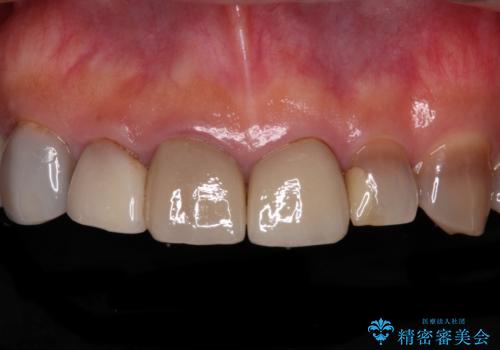

[ 歯が小さい ] 根管治療を伴う矮小歯治療

![[ 歯が小さい ] 根管治療を伴う矮小歯治療の症例 治療前](https://seimitsushinbi.jp/wp/wp-content/uploads/2021/09/c31c85cea60404f69948fd7103e8c7ca-500x350.jpg?v=1632883039)